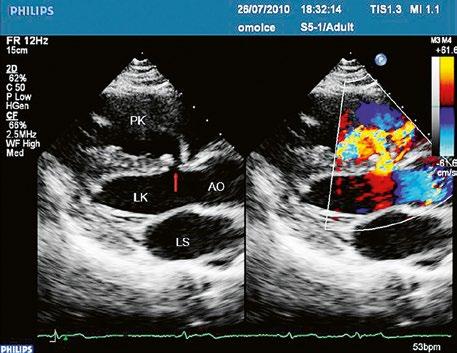

Poslechový nález systolického šelestu nad plicnicí s fixním rozštěpem 2. ozvy je nenápadný. Echokardiograficky je patrná dilatovaná a objemově přetížená pravá komora s paradoxním pohybem septa (Obr. 45.9), zkratový tok může být vidět i transtorakálně (TTE) (Obr. 45.10, Video 45.3, Video 45.7), ale suverénní diagnostickou metodou je jícnová echokardiografie (TEE), případně s 3DE zobrazením (Obr. 45.1, Obr. 45.2,

Obr. 45.10 TTE, čtyřdutinová apikální projekce s levo pravým zkratem na úrovni síní (šipka) při defektu septa síní typu secundum PK – pravá komora, LK – levá komora, LS – levá síň, PS – pravá síň